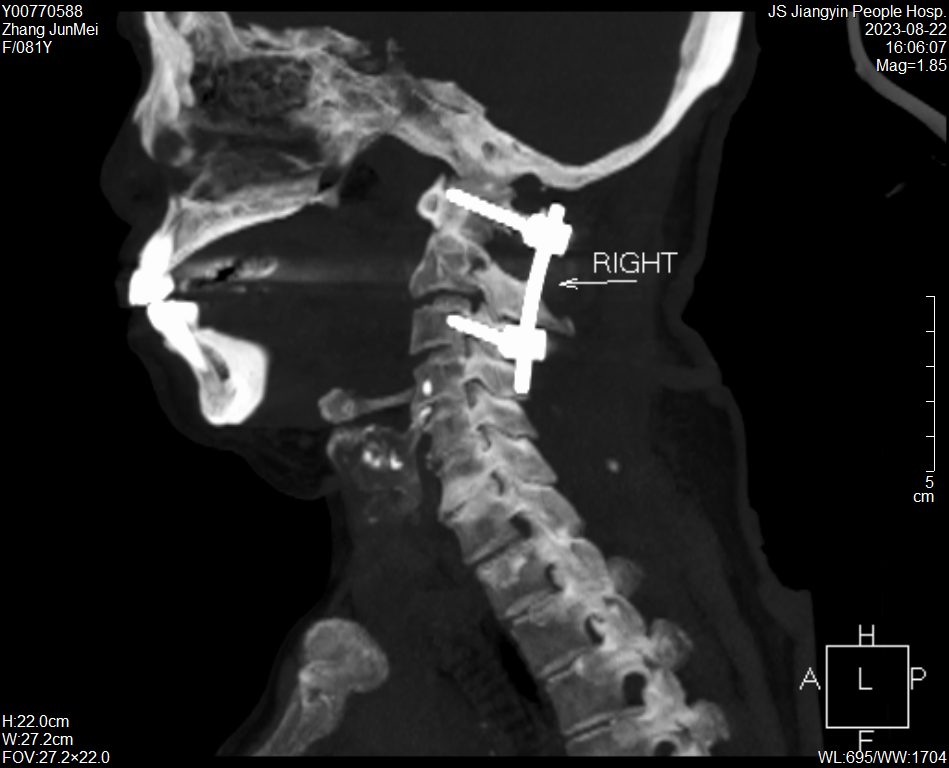

張奶奶術(shù)后CT

術(shù)后第2天,老人就佩戴頸椎支具下床活動(dòng)。目前,張奶奶病情恢復(fù)良好,穩(wěn)步康復(fù)中。